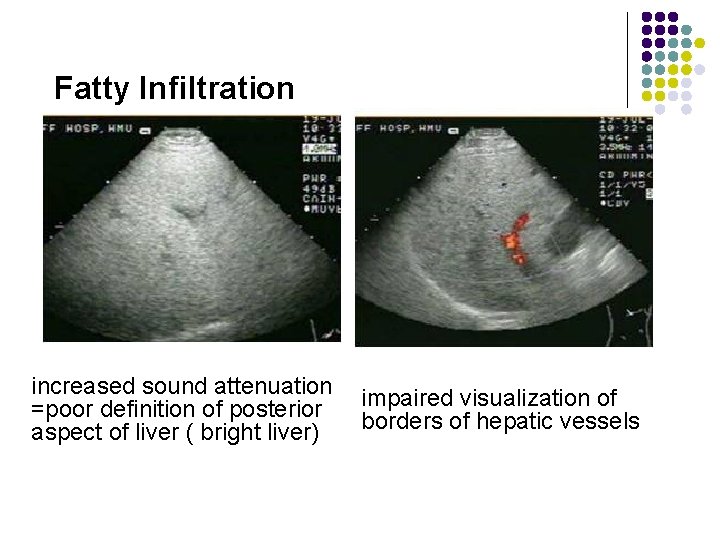

Pathology of the Live Diffuse Fatty Infiltration US l increased sound attenuation =poor definition of posterior aspect of liver ( bright liver) l fine/coarsened hyperechogenicity (compared with kidney) l impaired visualization of borders of hepatic vessels l Attenuation of sound beam

Fatty Infiltration increased sound attenuation =poor definition of posterior aspect of liver ( bright liver) impaired visualization of borders of hepatic vessels